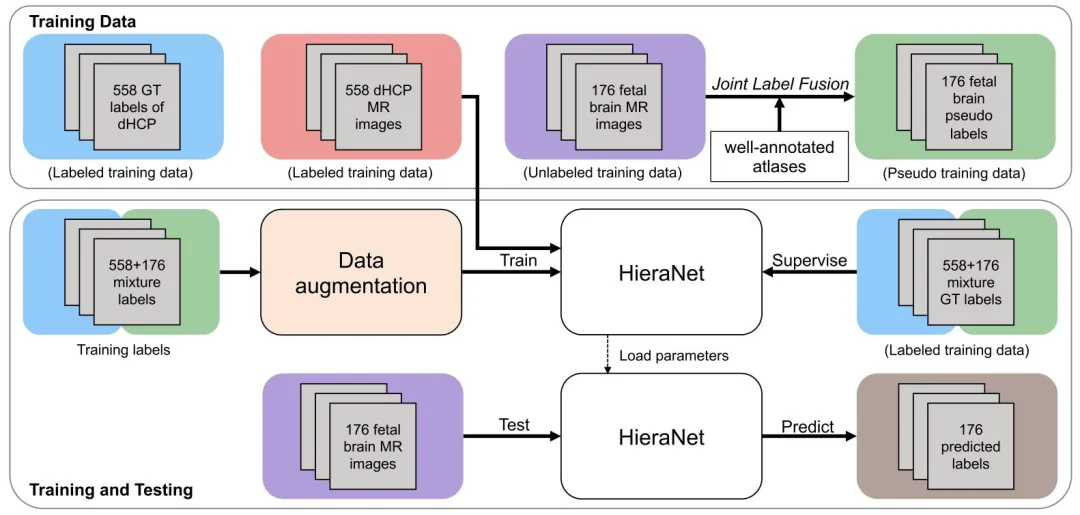

Fig. 4. Overview of the proposed Semi-supervised HPNet framework

图4 所提半监督HPNet框架概述